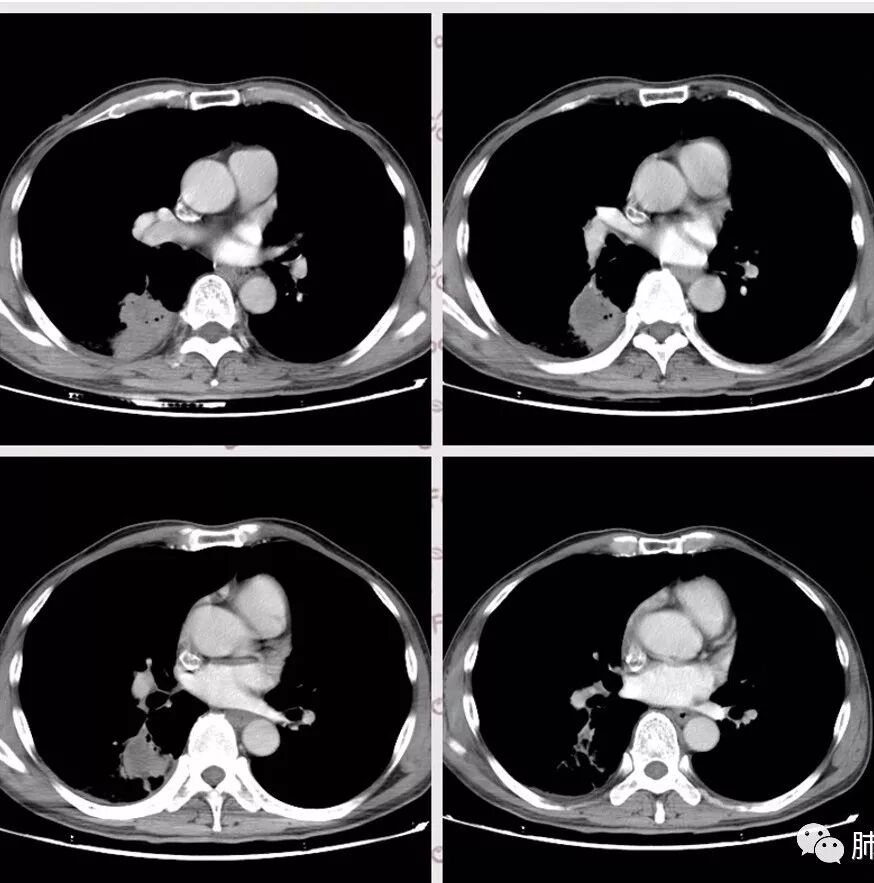

右肺下叶团块状密度增高影,边缘模糊,其内见液性低密度影,多发小气泡影及充气支气管征,考虑肺脓肿。颅内双侧顶叶长T2长T2病灶,周围水肿,DWI高信号,增强扫描囊壁环形强化,囊壁钙化,周围水肿,考虑脑脓肿。患者长期接触垃圾,什么菌都有,肺、脑脓肿,考虑肺克。再有肝脓肿就更支持了。

慢性病程,体质一般、接触垃圾,右下肺长轴与胸膜平行肿块,近肺门侧液化坏死伴多个小圆型空泡,肿块密度不均、不均匀强化,周围少量胸膜增厚,脑内多发空洞灶,考虑肺脑脓肿。鉴别肺腺癌脑转移。

头是脓肿,没有糖尿病;胸膜下分布为主,轻中度强化,实变中坏死,结合头颅表现,考虑隐球菌病,肺克。

胸部CT:右肺下叶背段实变,广基底,糊墙,长轴与胸膜平行,周围晕,支气管进入堵塞,纵隔窗可见低密度坏死,实变内小空洞?脑部不会看。

胸CT:右肺下叶背段实变影,内可见小空泡,病灶与胸膜呈宽基底,实变病灶周围存在毛玻璃影,纵隔窗可见病灶内存在低密度,增强可见病灶强化,并见病灶内低密度区。头MRI不会看。

右肺下叶背段实变,广基底,糊墙,长轴与平行胸膜,周围有晕,支气管进入堵塞,可见低密度坏死及小空泡。颅内多发环形强化灶,符合脑脓肿三层结构,结合临床,考虑:感染性病变,隐球菌?鉴别肺克。

肺内类三角形稍高密度病灶,边缘模糊,其内看见两个小气泡影。增强扫描欠规则厚壁中度强化,其内有轻度强化或未强化区。符合肺脓肿表现。

右肺下叶见不规则软组织影,边缘不清,内夹杂气体,背段支气管未见明显阻断,增强扫描下叶病灶内见类圆形低强化区,其边缘光滑,见低强化区壁,颅脑左侧枕叶及双侧顶叶见多发长T1长T2信号,T2高信号内见类圆形异常信号,壁呈低信号,DWI环形壁未弥散受限,内容物弥散受限,周围为水肿区,增强扫描呈多发环形强化,考虑血源型感染,颅内及右肺下叶脓肿形成

蔡磊:

肺部病灶有收缩性,支持感染性病变,但是患者病程不急,不支持肺克

右肺下叶大片实变

我们回头看肺内的,病灶位于下叶背段,可惜没重建

近肺门区见一坏死腔,内壁较清楚,空泡在周围

单从这个坏死我们分析:1、炎性?2、鳞癌?

局部部分边缘膨隆,欠光滑

不是单纯的近端堵塞,远端不张,远端实变,宽基底

远端实变区膨隆,部分似有栽赃的趋势

感染一定有,但是应该还有警惕癌

南边:

一般来说炎性空洞坏死,空洞偏内的结核多,癌性空洞一般是远端的缺血坏死,这个病例特殊,近端支气管显示不清,内壁部分清晰,部分不清晰,是不是层厚的问题?

炎性有。从总体来说,病变分两部分,靠肺门这里是一个弧形的。从影像来说,确实有些壁不是很清楚,层厚、窗宽窗位影响,这个壁细节显示不是那么清楚。大点病灶是一个有分叶的,宽基底在外侧,病灶边缘有膨隆的迹象。

少量积液反衬外壁更好看,靠近胸膜侧有很多积液不连续,断掉,局部膨隆在外面。很大一部分是连续的,但有些部分是不连续的。有膨隆我就很难判断,病灶的膨隆是张力引起的,还是远端栽赃引起的?局部的胸膜有变化的。所以我怀疑有栽赃的趋势,为什么说趋势,是因为没看到外面一个侵犯的迹象,但是层厚原因我有些地方我不敢说,有没有侵犯。

你看我标的这个地方,我就觉得这个病灶有侵犯性,附近旁边都有一个低密度线影,局部就没了,病灶似乎直接到个肋骨的胸膜脂肪间隙下,这些地方都有类似迹象,把它当成一个大的肿块,有分叶,近端有坏死、空洞,壁外围还有有些毛糙,腔内也有些索条影。颅脑内像个转移瘤的特点,转移瘤,淋巴瘤,脓肿?脓肿腔内脓液粘稠,弥散受限,这个腔内DWI不高,这个让我犹豫.按理脓肿也要考虑.

2.影像右肺下叶大片高密度影,整体边界模糊柔和,中央见圆形液化区及微小气泡影,内壁相当光整,环形强化,未见明确壁结节。双肺门及纵隔未见增大淋巴结。这样的病灶更符合细菌性肺脓肿,以肺炎克雷伯杆菌感染最为常见。